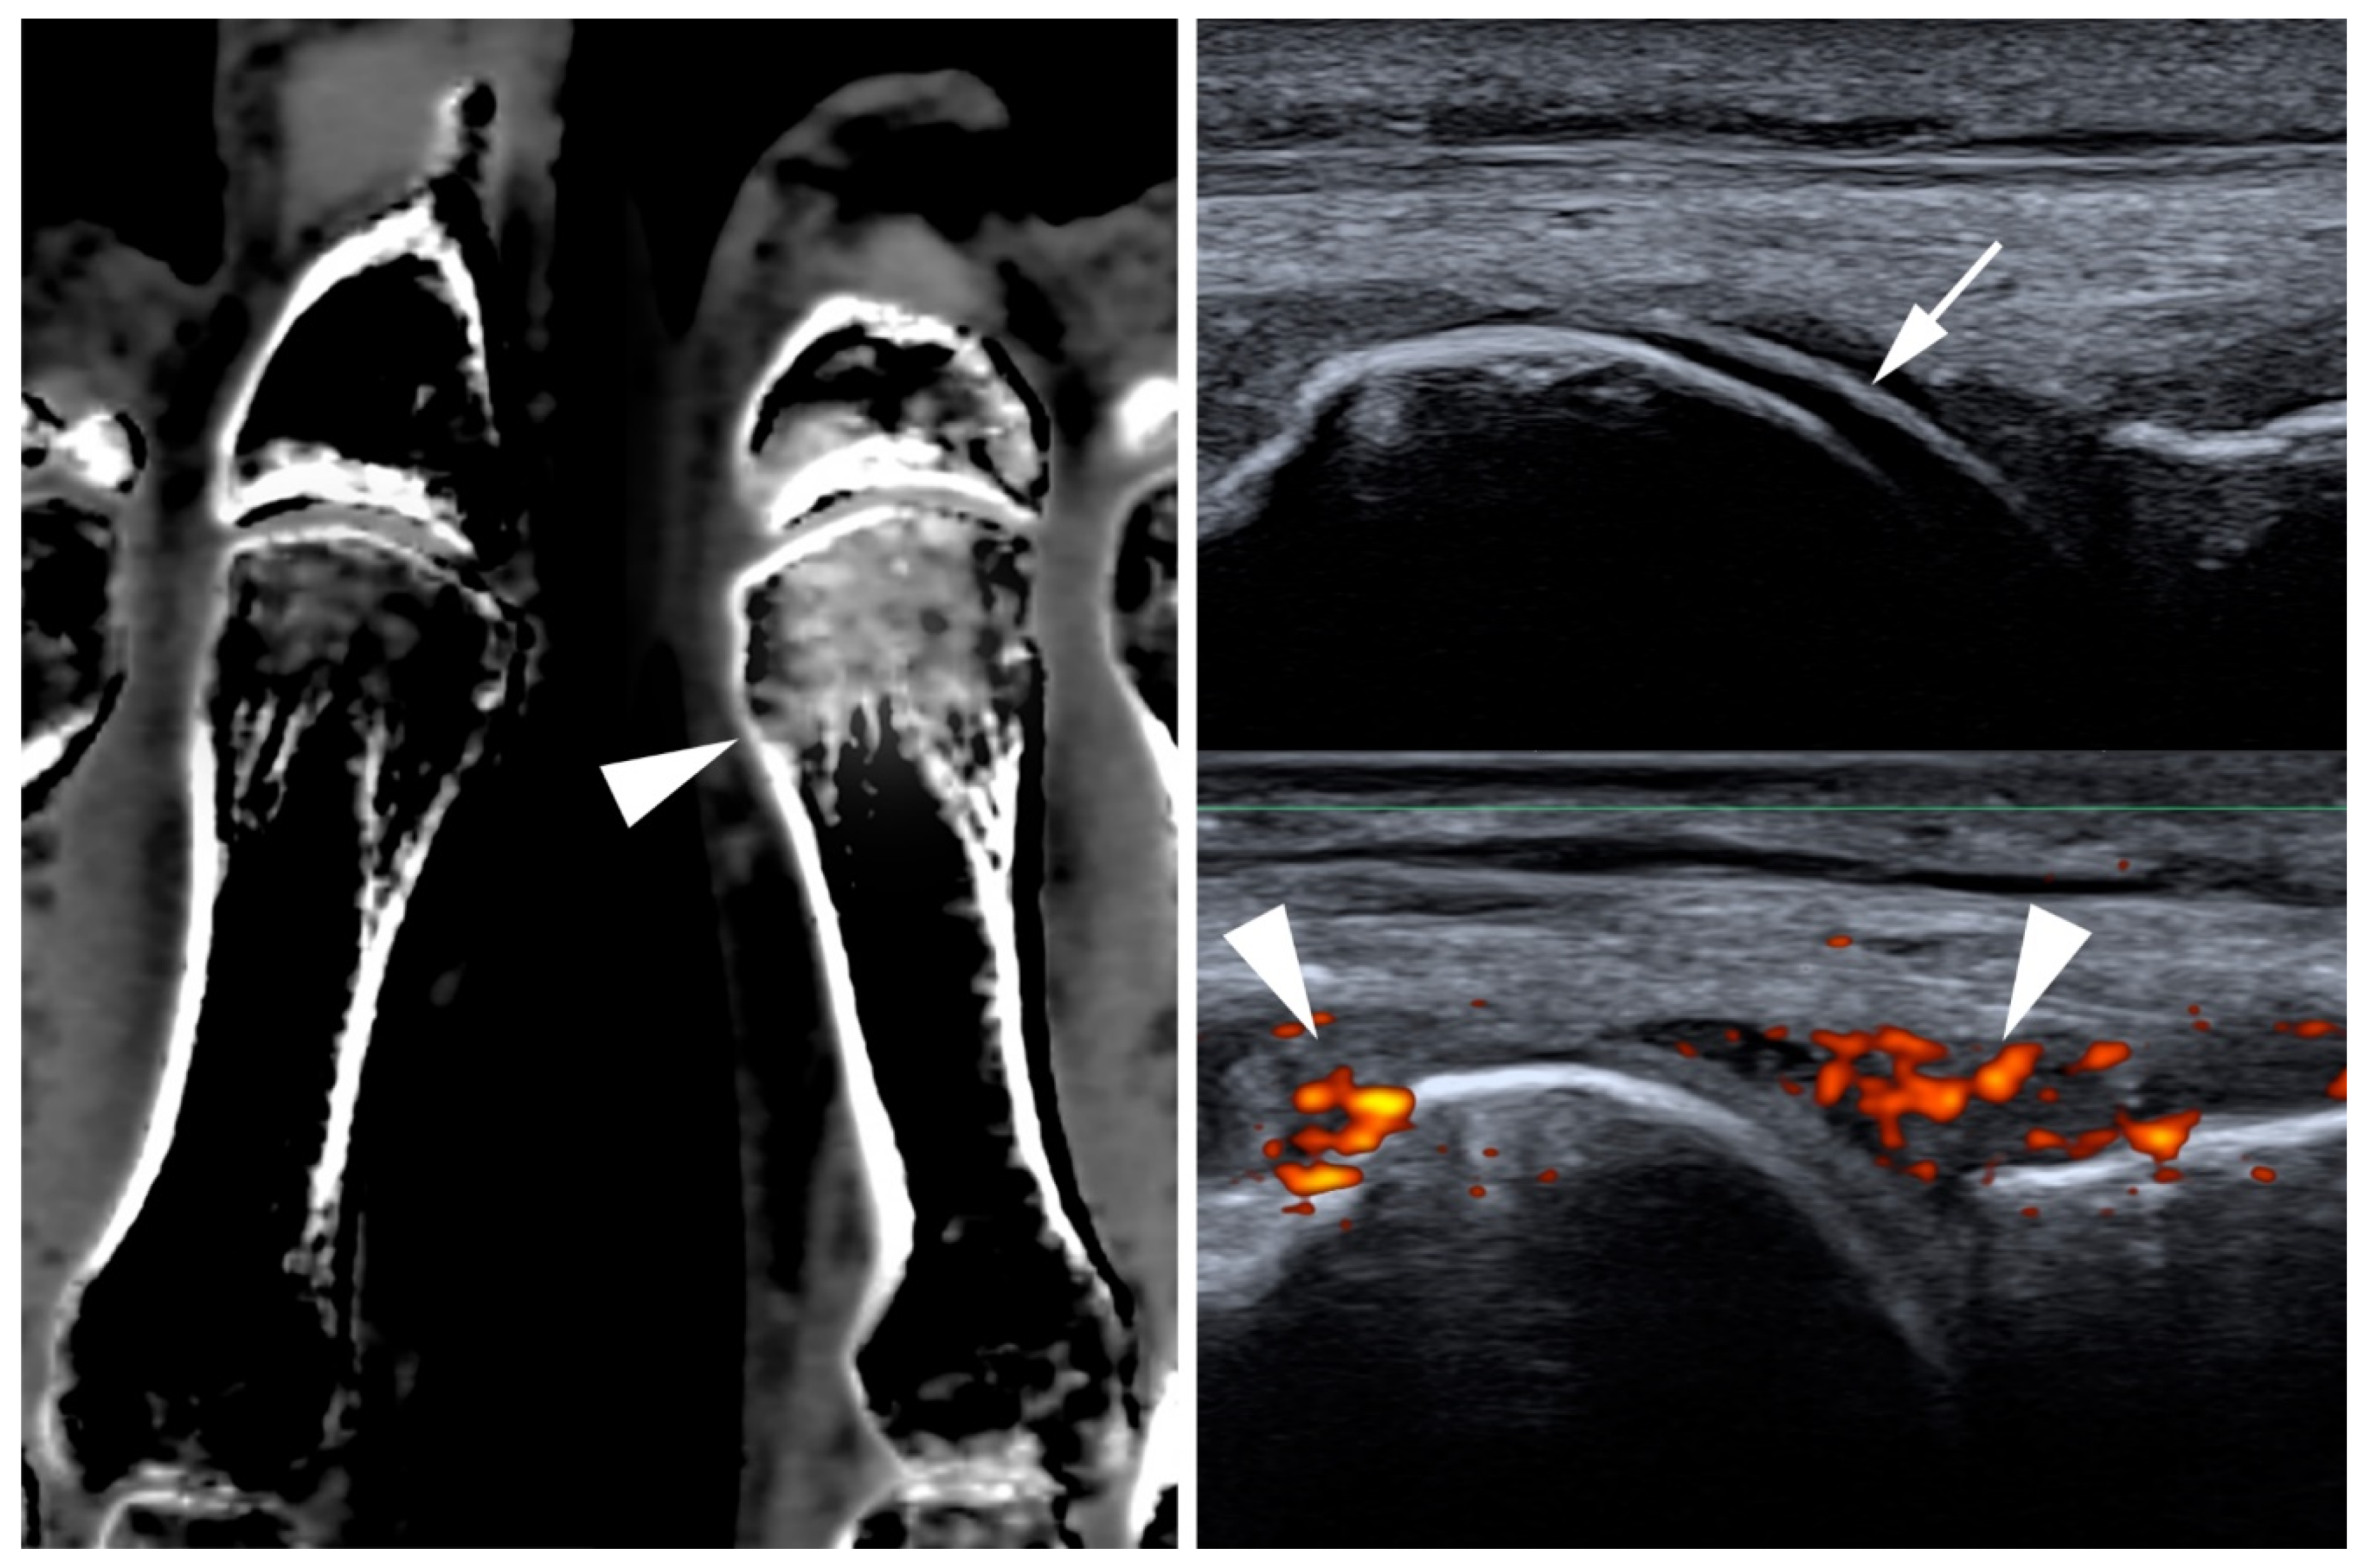

- Checa, A. Consistency of the sonographic image (double contour sign) in patients with gout after ambulation. J. Med. Ultrasound 2019, 27, 40–42. [Google Scholar] [CrossRef]

- Ogdie, A.; Taylor, W.; Neogi, T.; Fransen, J.; Jansen, T.L.; Schumacher, H.R.; Louthrenoo, W.; Vazquez-Mellado, J.; Eliseev, M.; McCarthy, G.; et al. Performance of Ultrasound in the Diagnosis of Gout in a Multicenter Study: Comparison with Monosodium Urate Monohydrate Crystal Analysis as the Gold Standard. Arthritis Rheumatol. 2017, 69, 429–438. [Google Scholar] [CrossRef] [PubMed]

- Ogdie, A.; Taylor, W.J.; Weatherall, M.; Fransen, J.; Jansen, T.L.; Neogi, T.; Schumacher, H.R.; Dalbeth, N. Imaging modalities for the classification of gout: Systematic literature review and meta-analysis. Ann. Rheum. Dis. 2015, 74, 1868–1874. [Google Scholar] [CrossRef] [PubMed]

- Peiteado, D.; Villalba, A.; Martín-Mola, E.; Balsa, A.; De Miguel, E. Ultrasound sensitivity to changes in gout: A longitudinal study after two years of treatment. Clin. Exp. Rheumatol. 2017, 35, 746–751. [Google Scholar] [PubMed]

- Löffler, C.; Sattler, H.; Peters, L.; Tuleweit, A.; Löffler, U.; Wadsack, D.; Uppenkamp, M.; Bergner, R. In arthritis the Doppler based degree of hypervascularisation shows a positive correlation with synovial leukocyte count and distinguishes joints with leukocytes greater and less than 5/nL. Jt. Bone Spine 2016, 83, 517–523. [Google Scholar] [CrossRef]